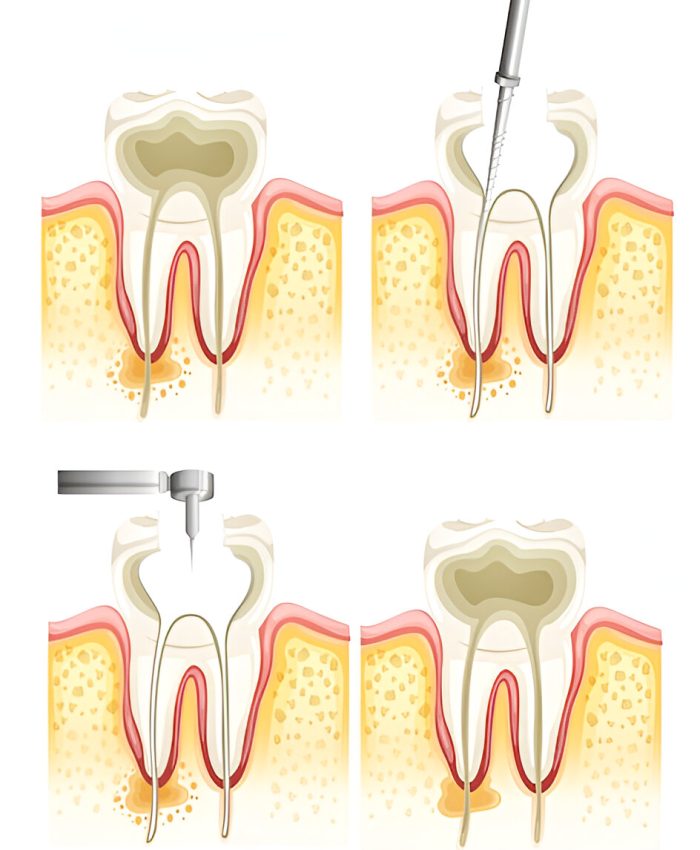

Deep Cleaning for Gum Disease

The performance of Scaling and Root planning functions to remove below-gumline plaque and tartar then makes root surfaces smooth for reducing regrowth.

Surgical Solutions

We perform flap surgery combined with bone grafting procedures to treat serious gum disease which helps maintain gum condition.